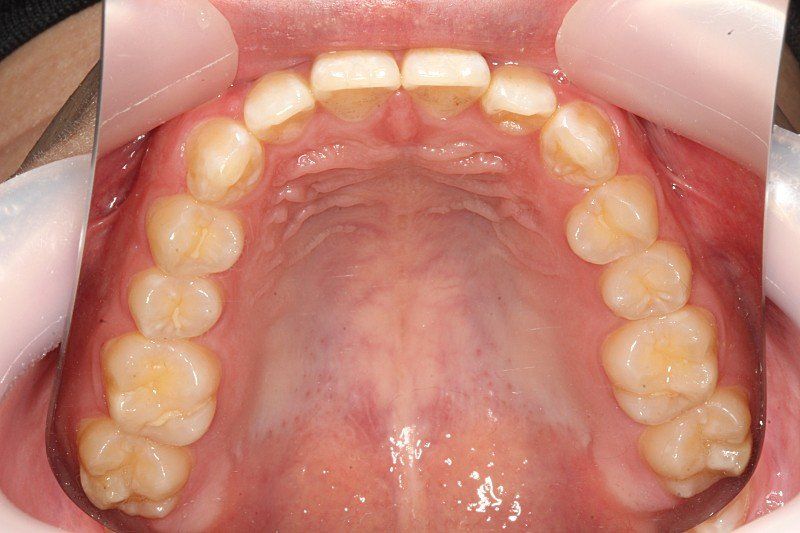

치과에서 사진찍었는데 사진을 보니 잇몸이 돌출된 느낌이 들어서요 치아 각도는 정상같아 보이는데 잇몸이 전체적으로 앞으로 쏠린느낌이 듭니다

잇몸도 다른분들은 붉은색이나 선홍색을 띄는데 저는 치아 뼈 때문인지 하얀색도 많고 울퉁불퉁 한 느낌이에요

• 3번 째 사진